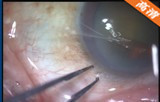

该手术透明角膜切口,注入粘弹剂 ,辅助切口;,连续环形撕囊;水分离、水分层; 超声乳化吸除晶状体核 ,灌注抽吸手柄(I/A)抽吸出残留的晶状体皮质; 后囊膜抛光 ,注入粘弹剂 。植入折叠人工晶体, 吸除医用透明质酸钠凝胶 ,水密切口 。